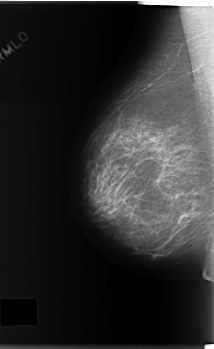

C_0165_1.RIGHT_MLO

RIGHT_CC LINES 5896 PIXELS_PER_LINE 3424 BITS_PER_PIXEL 12 RESOLUTION 50 NON_OVERLAY

RIGHT_MLO LINES 5920 PIXELS_PER_LINE 3632 BITS_PER_PIXEL 12 RESOLUTION 50 NON_OVERLAY